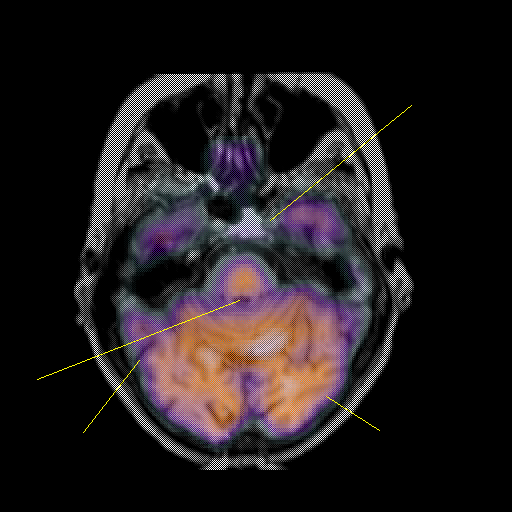

overlay: Slice 16

Slice 16

MRCBFCBF with

Unlabeled

Pointers

Labeled